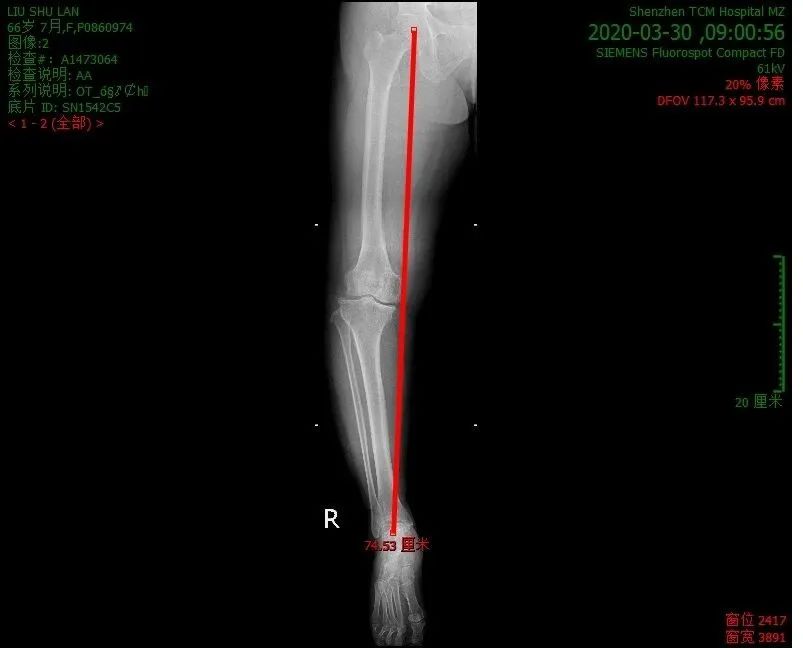

X线检查:

X线平片为最常用的骨关节影像学检查技术。在显示关节间隙狭窄、关节面硬化和变形、边缘性骨质增生和骨桥、关节面下囊性变、关节内游离体、钙化、骨质破坏和疏松等方面具有相当的价值。

内翻畸形示意图